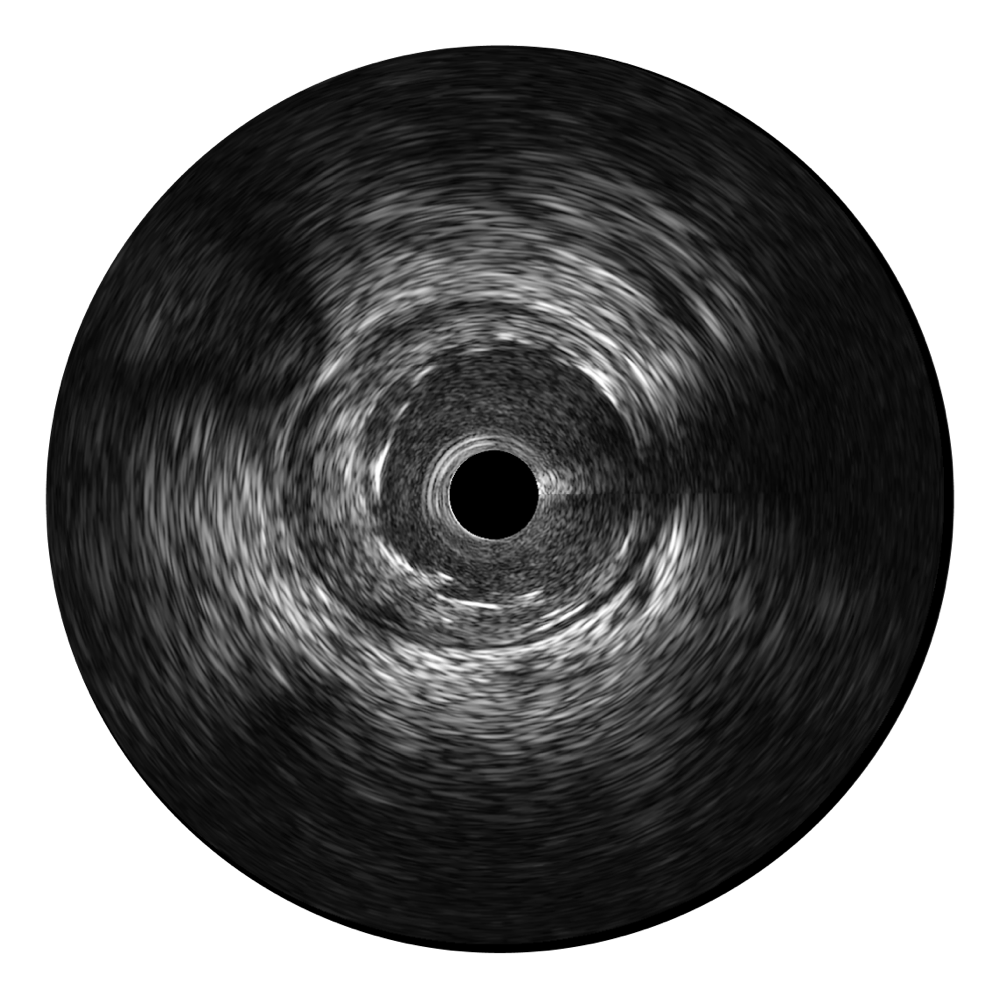

• 云顶集团官网宽频IVUS图像

对比传统IVUS导管成像,云顶集团官网宽频IVUS图像的近场支架梁显影更细腻,远场中膜外血管仍清晰可辨,兼顾远中近,兼顾分辨力与穿透深度